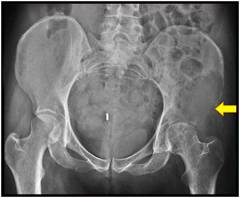

Рентгенография Рентгенологическое исследование копчика осуществляется в двух проекциях – передней и боковой. Для снимка передней проекции копчика больного следует уложить на спину и попросить вытянуть ноги. Для того чтобы сделать рентгенограмму боковой части копчика больному необходимо лечь набок и согнуть ноги в коленных и тазобедренных суставах.

Позволяет диагностировать следующие патологические изменения в области копчика:

• переломы;

• вывихи и подвывихи;

• аномальные наросты;

• трещины;

• межпозвоночные грыжи;

• ущемления спинного мозга;

• гнойники и абсцессы;

• ишиас (защемление седалищного нерва).